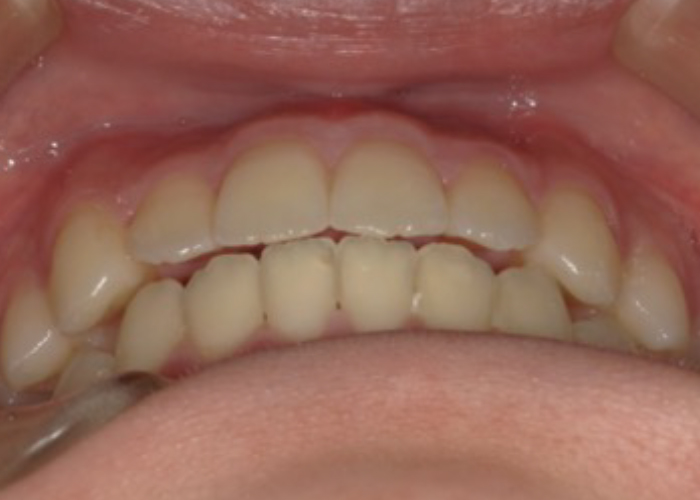

前歯の見た目を改善したい

前歯の歯並びを改善したい